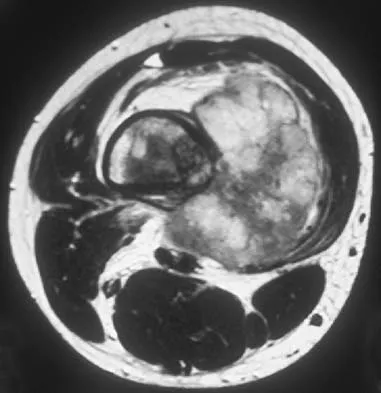

A 22-year-old professional baseball catcher has posterior shoulder pain and severe external rotation weakness with the arm in adduction. Radiographs are normal. MRI scans are shown in Figures 15a through 15c. Management should consist of

The MRI scans reveal a large posterior paralabral cyst associated with a posterior-superior labral tear. The cyst appears as a well-defined, smoothly marginated mass with low signal intensity on T1-weighted MRI scans and with high signal intensity on T2-weighted MRI scans. MRI also reveals changes in the supraspinatus and infraspinatus muscles secondary to denervation, including decreased muscle bulk and fatty infiltration. MRI has the added advantage, compared with other imaging modalities, of detecting intra-articular lesions, such as labral tears, which are frequently associated with ganglion cysts of the shoulder. In this case of a professional baseball player with a space-occupying lesion causing nerve compression with an associated labral tear, the treatment of choice is arthroscopic decompression of the cyst and repair of the tear. Acromioplasty would not address the primary pathology in this patient. Cummins CA, Messer TM, Nuber GW: Suprascapular nerve entrapment. J Bone Joint Surg Am 2000;82:415-424.